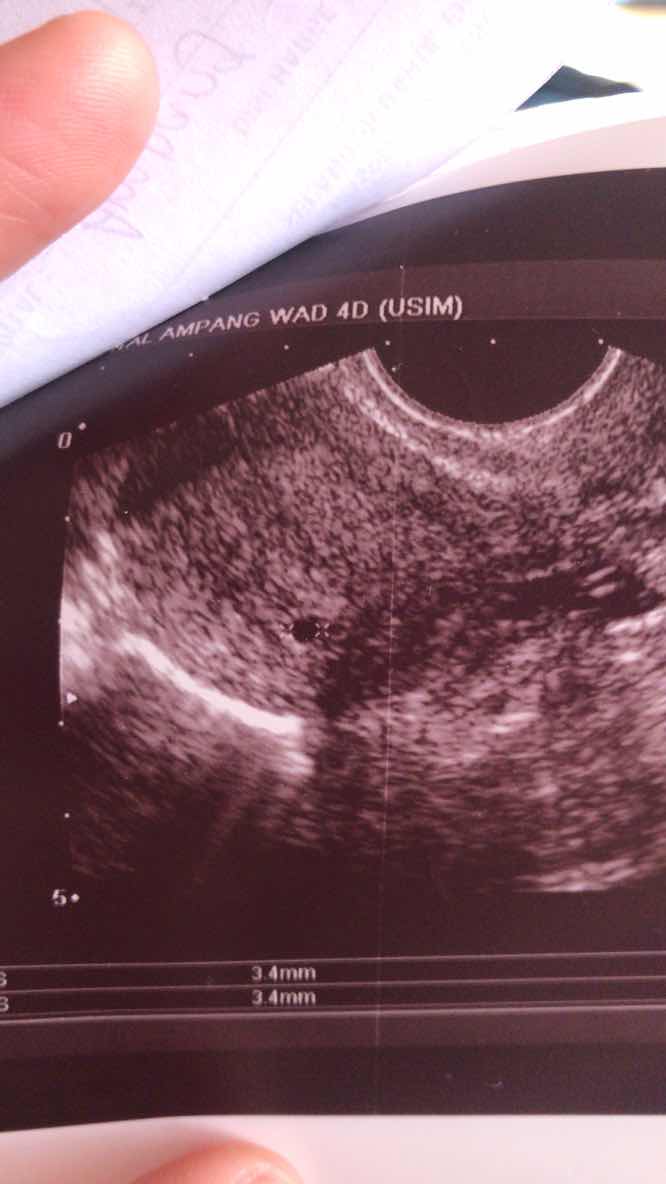

Kemarin saya pergi klinik, scan. anggaran saya pregnant dah 9 minggu. scan sana sini, takde kantung & baby ? susah hati sangat. Klinik tu suruh saya pergi hospital untuk scan bawah pula. Sampai terus scan ikut bawah, pun tak ada. Doctor ni jumpa bulat kecik & suspek saya kandungan anggur. luluh hati ni sampai tak terkata, sepatutnya kemarin saya kena tahan ward & saya kena buang kandungan anggur tu. kali ke 5 scan, doctor pakar pulak kata mungkin saya bukan kandungan anggur, ni salah tarikh. nasib baik setiap kali saya buat UPT mesti amik gambar, check balik tarikh. 13/11 saya masih negative, UPT start positive 18/11. Doctor kata tak mungkin kandungan 2bulan tapi 13/11 tu masih negative. ni sah salah tarikh. Klinik cuma bagi anggaran sahaja, bila diukur kantung tu, kemungkinan kandungan saya baru 5 minggu. 3 hari saya tidur tak lena, lepas doctor pakar cakap macam tu. Alhamdullilah lega hati. tapi lega tu tak sepenuhnya, tersimpan sikit rasa risau. harap2 dua minggu lagi kantung saya & baby dah boleh nampak ? insyallah, serah pada Allah je ni. 2 tahun berharap, hari pertama positive, bahagia tu Allah je tahu. tak apa lah, kita hanya mampu merancang & Allah yang menentukan. Saya minta mommy2 dekat luar sana, tolong doakan saya & anak saya ye??

semalam & petang tadi saya pergi klinik swasta untuk check kandungan membesar atau tidak. pergi klinik dr nurul, tiba2 scan tak nampak apa. kena pulak pergi hospital, hospital pun tak nampak kantung atau apa2. sampai dr syak saya kandungan anggur, kali ke 3 scan doctor pakar yang check & dia kata ikutkan kedudukan ni bukan kandungan anggur tapi ni kantung kecil & salah tarikh due date. kalau lah doctor pakar tu tak check, rasanya malam ni tahan wad & esok pagi kena keluarkan “kandungan anggur” tu. nasib baik lah dr bagi balik & datang dua minggu lagi. harap2 betul lah kandungan masih kecil ? sayu hati bila dalam excited ni ttbe sebenarnya anak tu tak ada. susah nak tgok suami sedih, bila jdi mcm ni dia pun nangis?